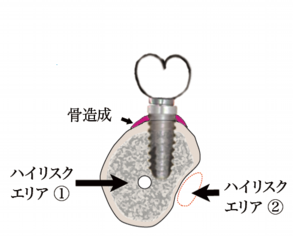

インプラントの噛み合わせの重要性が見直され、きちんとした噛み合わせが大事ということが証明されたのち、かぶせの歯の位置を決めた後にインプラントをいれるという順序にかわりました。しかしこの治療はCTが必ず必要となり、また経験が必要とされる骨造成も必要になることが多く、絵のようにハイリスクエリアに近接してしまうこともありますので、トラブルもやはり存在しています。